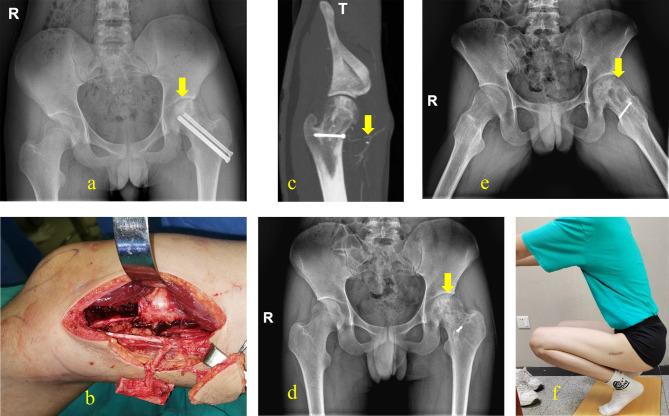

Fifteen cadavers were arterially perfused with red latex and dissected. Thirty-one patients with extremity tissue defects were treated with a free DGAP flap, including six patients who received a chimeric flap. The minimum distance between the DGAP and the SV was measured during surgery.

In all patients, the skin branch of the descending genicular artery was found in the medial femoral condyle plane in front of the SV. The average distance between the descending genicular artery perforator and the SV was 3.71 ± 0.38 cm (range: 2.9-4.3 cm). Thirty flaps survived completely, and one flap developed partial necrosis; however, this flap healed two weeks after skin grafting. The average follow-up time was 11.23 months.

We conclude that the SV can be preserved when harvesting the descending genicular artery perforator flap, causing less damage to the donor site and having no effect on flap survival. The free descending genicular artery perforator flap without the SV is a better therapy for complicated tissue defects.